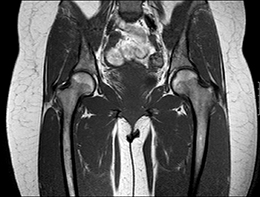

In der MRT, die auch als Kernspintomographie bezeichnet wird, kommen keine radioaktiven Strahlen zum Einsatz. Die Bildgebung erfolgt durch Signale, die für den Menschen unschädlich sind. Mit Hilfe eines außerordentlich starken Magnetfeldes werden die Wasserstoffkerne in den Molekülen der verschiedenen Gewebe des Körpers wie Kompassnadeln ausgerichtet. Durch Änderung des Magnetfeldes und wiederholter Sendung von Frequenzimpulsen schwingen sie in ihre ursprüngliche Lage wieder zurück, wobei sie ihrerseits Signale aussenden, die in einem Hochleistungscomputer in Schnittbilder umgewandelt werden.

Die MRT ist hinsichtlich der Darstellbarkeit von verschiedenen Organen, Gefäßen, Bändern und Gelenken vielen anderen heute in der Radiologie zur Verfügung stehenden bildgebenden Verfahren überlegen. Insbesondere Entzündungsherde und vitale Tumoren können mit der MRT häufig besser erkannt werden als mit anderen Verfahren.